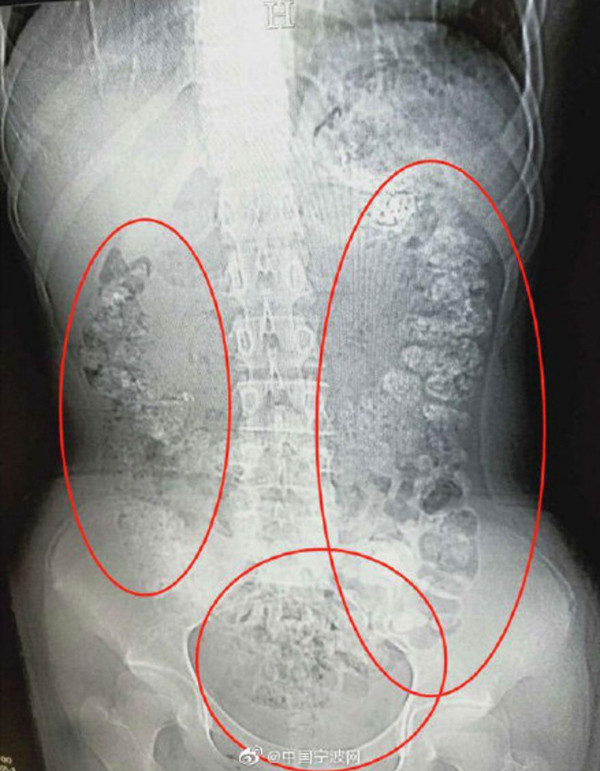

Có rất nhiều quả bóng hình cầu nhỏ chen chúc bất thường trong bụng bé gái 14 tuổi. Bác sĩ kết luận đây chính là các hạt trân châu trong trà sữa - một loại đồ uống đang rất được giới trẻ yêu thích.

| Ảnh chụp cho thấy có rất nhiều hạt trân châu bị kẹt trong bụng |

Sau khi gặng hỏi, bé gái cuối cùng đã thừa nhận bản thân rất mê trà sữa trân châu và vào 5 ngày trước đã uống sản phẩm này nhưng không chịu nói ra cụ thể số lượng đã dùng. Cuối cùng, cô bé được kê một vài loại thuốc nhuận tràng để trị bệnh.